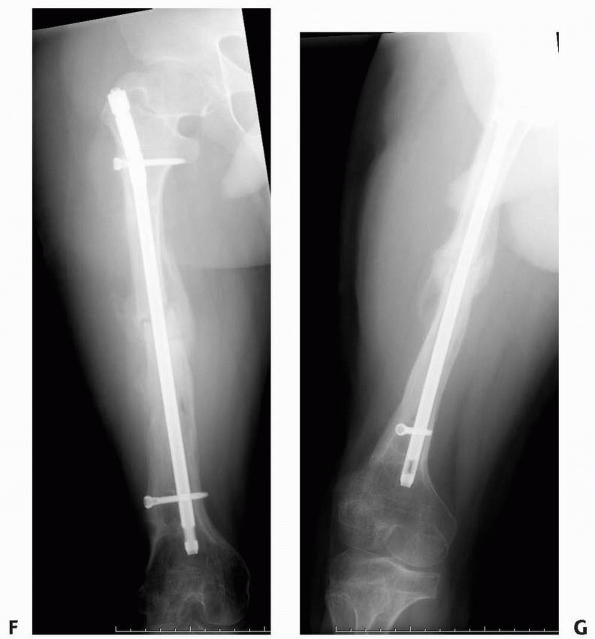

FIGURE 6-18

A 13-year-old boy presented with several months history of right arm pain and recent increase in pain following minor trauma. Anteroposterior (A) and lateral (B) radiographs show a minimally displaced midshaft humeral pathologic fracture through a poorly defined, permeative, aggressive-looking diaphyseal lesion. (C) T2-weighted axial MRI shows a huge soft tissue mass associated with the bone lesion and involvement of the neurovascular bundle. The patient was diagnosed with Ewing sarcoma, received neoadjuvant chemotherapy, and had a shoulder disarticulation (D), followed by postoperative chemotherapy. (Figures reproduced with permission from The Childrens Orthopaedic Center, Los Angeles, CA.) |